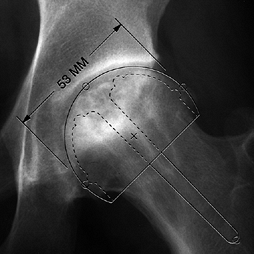

on the location and size of the lesion. Osteotomies may be utilized for

angle of less than 200° (Fig. 125.20) (65)

![]() |

|

Figure 125.20.

The angular measurements of the lesion on the AP and lateral radiographs are added together to give the “combined necrotic angle,” as described by Kerboul et al. (From Kerboul M, Thomine J, Postel M, Merle D’Aubigné R. The Conservative Surgical Treatment of Idiopathic Aseptic Necrosis of the Femoral Head. J Bone Joint Surg Br 1974;56:291, with permission.) |